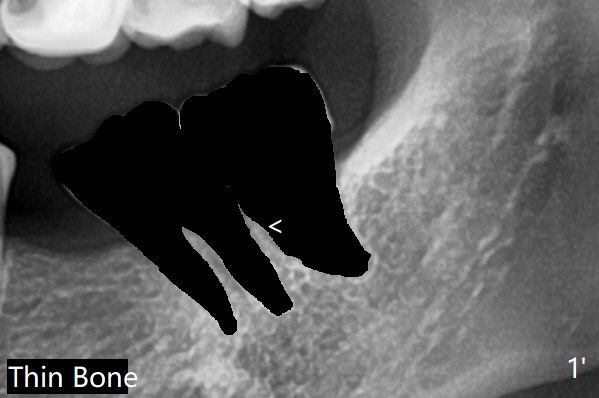

粘性骨粉植骨(图二:*)。术后一两个月(伤口愈合,18号牙牙冠远中面充分暴露)后,准备口扫做无形局部矫正(Clear Aligner),竖直18号牙。然后再口扫制作19号牙种植导板。